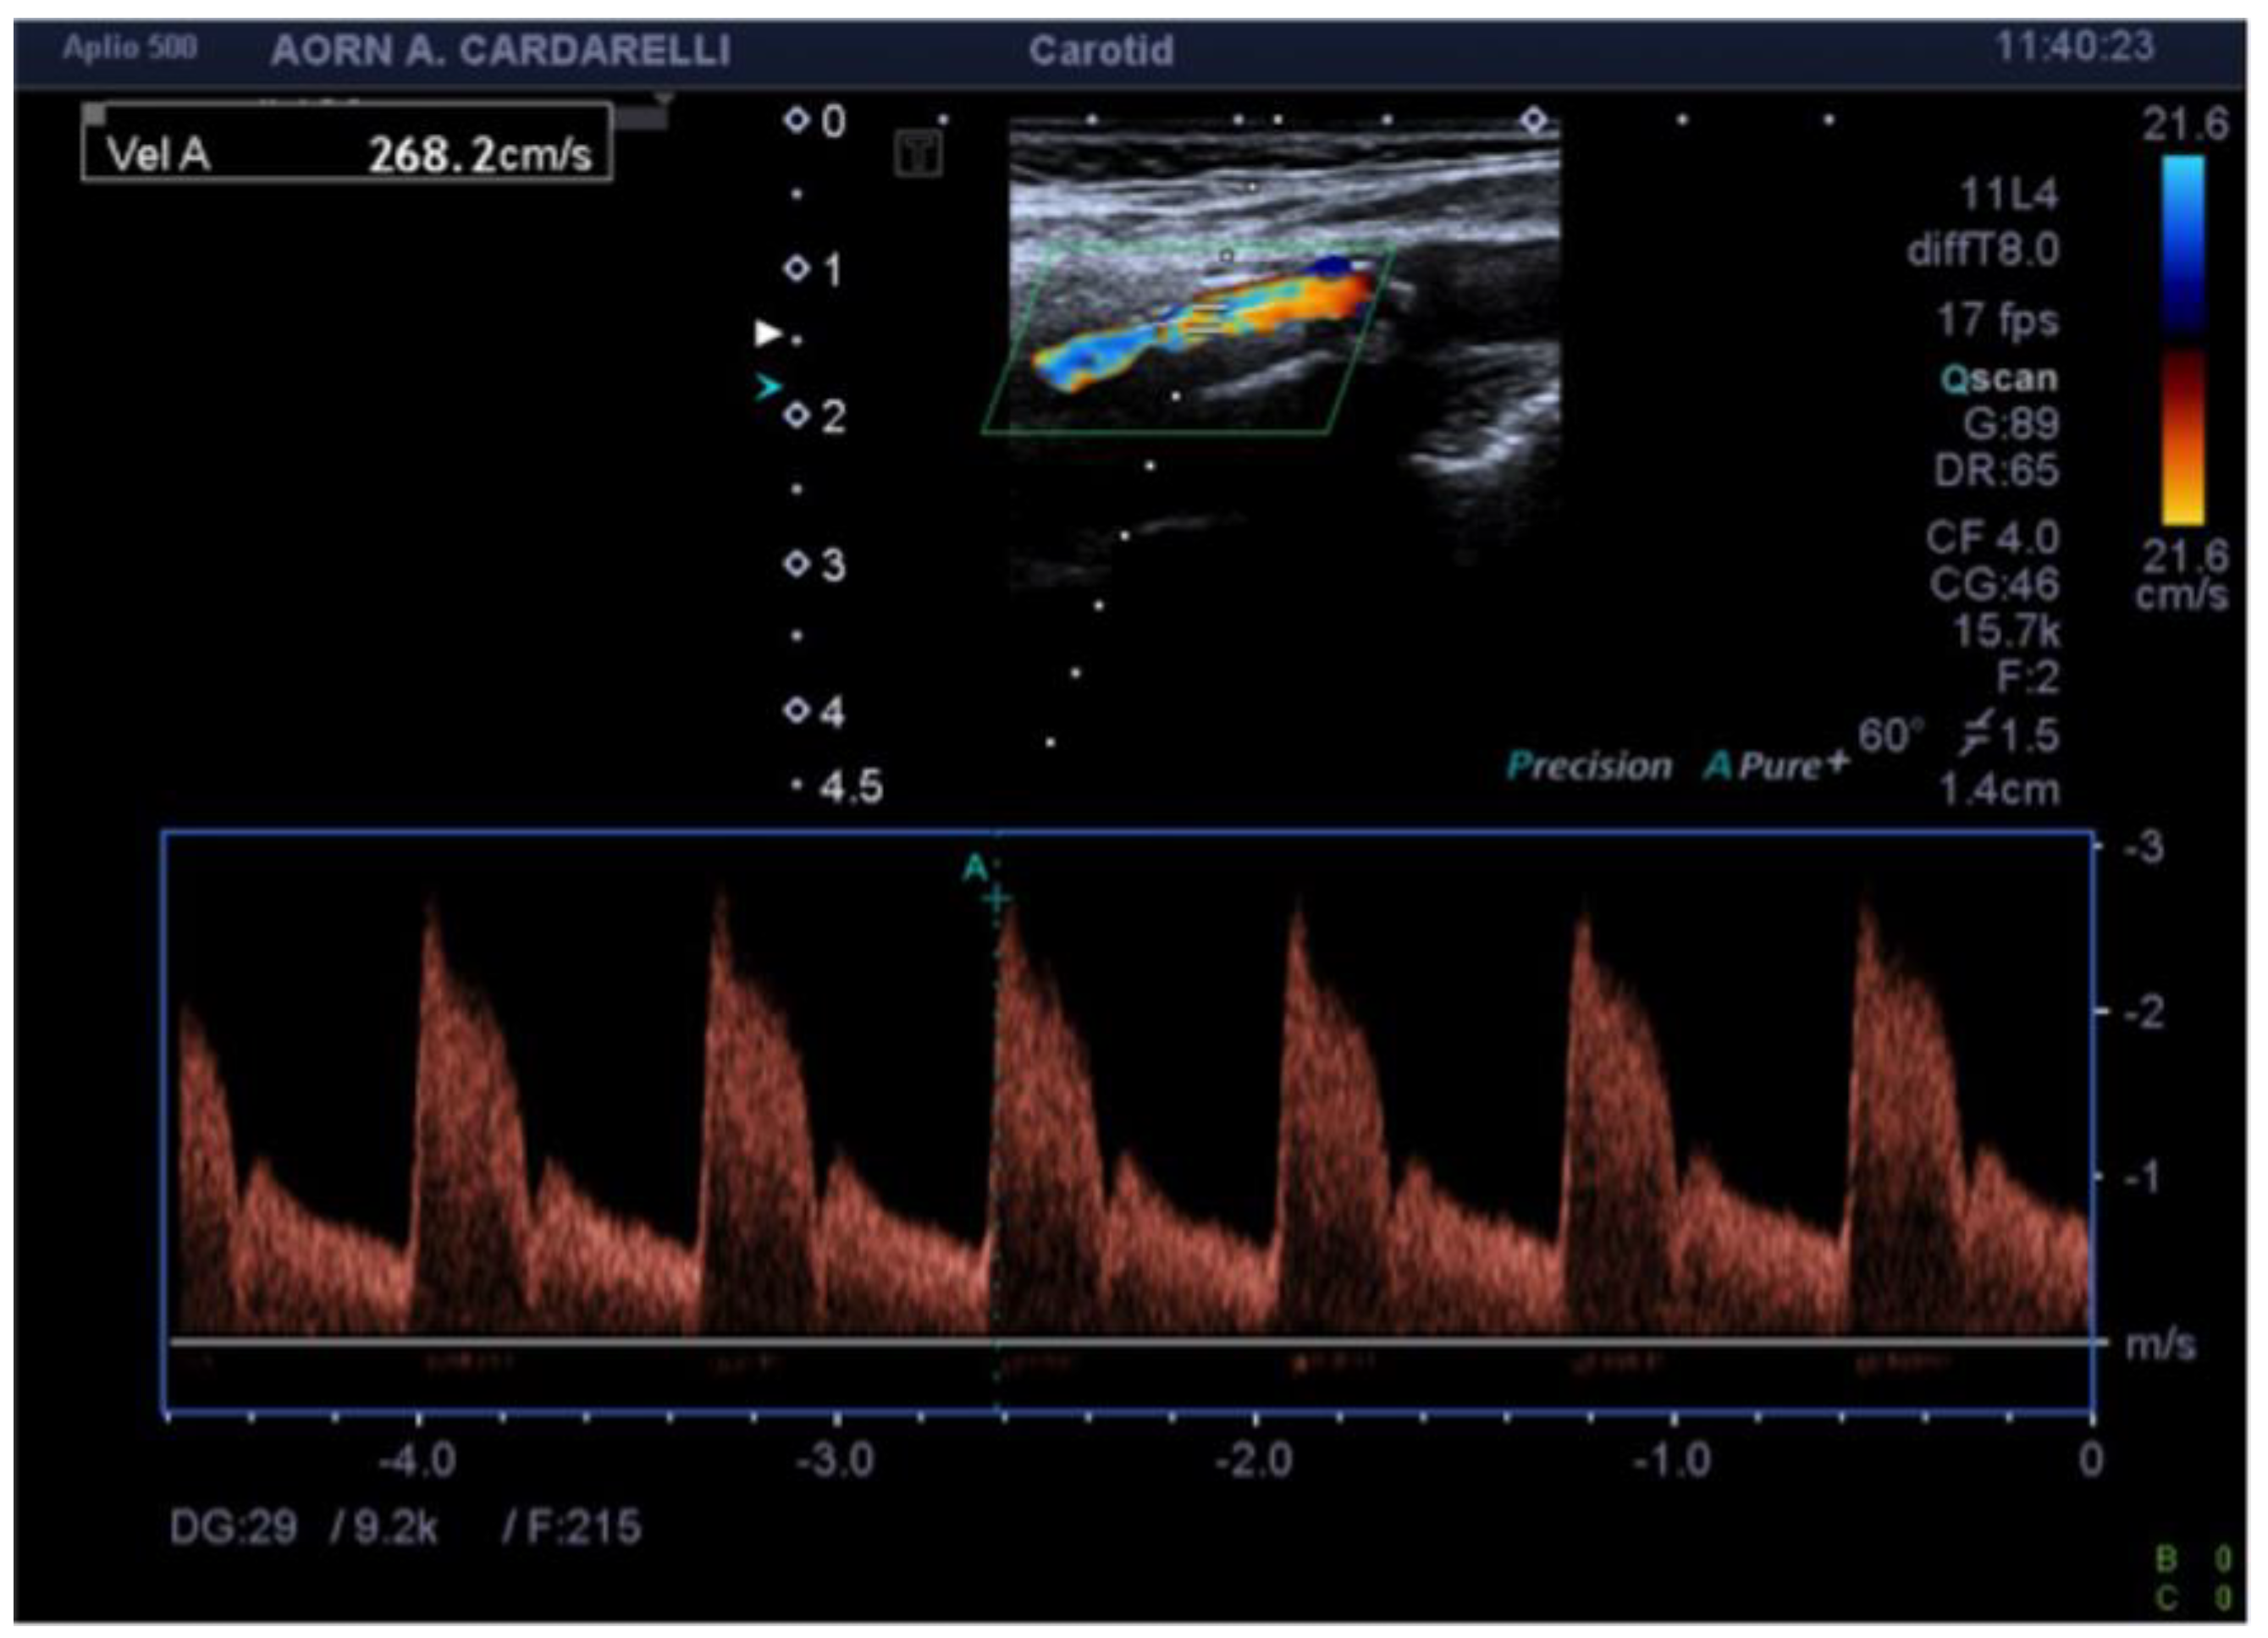

4. Color-Doppler Ultrasound (CDUS)